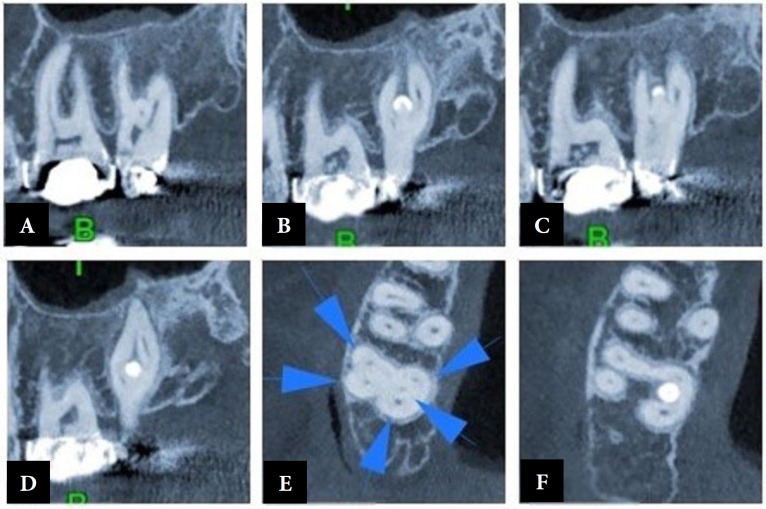

恒上颌第二磨牙的根管治疗由于其根结构的复杂性和根管系统的高度变异,是最成问题的牙齿之一。因此,临床医生应考虑不寻常的根管形态,以减少漏管率。一位三十岁的女性,因右上颌第二磨牙有明显的复发性龋齿,经修复后牙髓坏死而接受根管治疗。术前x线片显示不寻常的形态,并要求进行锥束计算机断层扫描以精确评估根管解剖。本文的主要目的是报道一个五根管上颌第二磨牙,两个腭根管和腭根状牙釉质珍珠管。

Permanent maxillary second molars' root canal treatment due to their root configurations complexity and high root canal systems variations, are one of the most problematic teeth. Accordingly, clinicians should consider unusual canal morphology to reduce the rate of missed canals. A thirty-year-old female was referred for root canal treatment of her maxillary right second molar tooth with obvious recurrent caries under restoration and necrotic pulp. Pre-operative radiographs showed the unusual morphology and cone-beam computed tomography was ordered for precise evaluation of the root canal anatomy. The principal aim of this paper is to report a five-root canals maxillary second molar, with two palatal root canals and a palatal root-like enamel pearl canal.